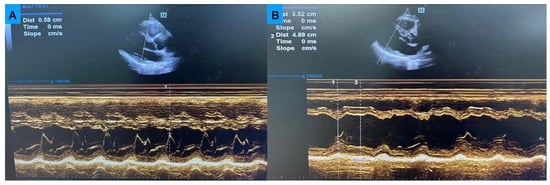

Diagnostic Value of Fractional Shortening and E-Point Septal Separation in Predicting Left Ventricular Longitudinal Strain in Dyspneic Emergency Patients

by Mustafa Ucar, Muhammed Ikbal Sasmaz, Doguhan Bitlisli and Akkan Avci

Medicina 2026, 62(2), 258; https://doi.org/10.3390/medicina62020258 - 26 Jan 2026

Background and Objectives: Dyspnea is a common chief complaint in the emergency department. While global longitudinal strain and biplane ejection fraction are reliable markers of left ventricular systolic function, their assessment requires advanced echocardiographic tools and expertise. Simple point-of-care ultrasound parameters, such as E-point septal separation and fractional shortening may serve as practical alternatives for rapid bedside evaluation. Materials and Methods: EPSS and FS were measured by emergency physicians using POCUS, while reference EF and GLS were obtained by cardiologists via transthoracic echocardiography. Correlation analyses, receiver operating characteristic curves, and agreement statistics were used to evaluate the diagnostic accuracy of EPSS and FS for predicting reduced EF (<50%) and GLS (<16%). Results: Reduced EF was present in 54.0% and reduced GLS in 55.6% of patients. EPSS showed strong negative correlations with EF (ρ = −0.834) and GLS (ρ = −0.782), while FS correlated positively with EF (ρ = 0.773) and GLS (ρ = 0.714), all p < 0.001. ROC analysis demonstrated excellent diagnostic accuracy of EPSS (AUC = 0.922 for EF; 0.949 for GLS) and good accuracy of FS (AUC = 0.874 for EF; 0.865 for GLS). Optimal cut-off values were EPSS ≥ 7.0 mm and FS ≤ 25%. Agreement with reference TTE was good for EPSS (κ = 0.676 for EF; κ = 0.738 for GLS) and moderate for FS (κ ≈ 0.56). Conclusions: Both EPSS and FS measured by POCUS provide reliable estimates of left ventricular systolic function in dyspneic ED patients, with EPSS demonstrating superior diagnostic performance. Full article